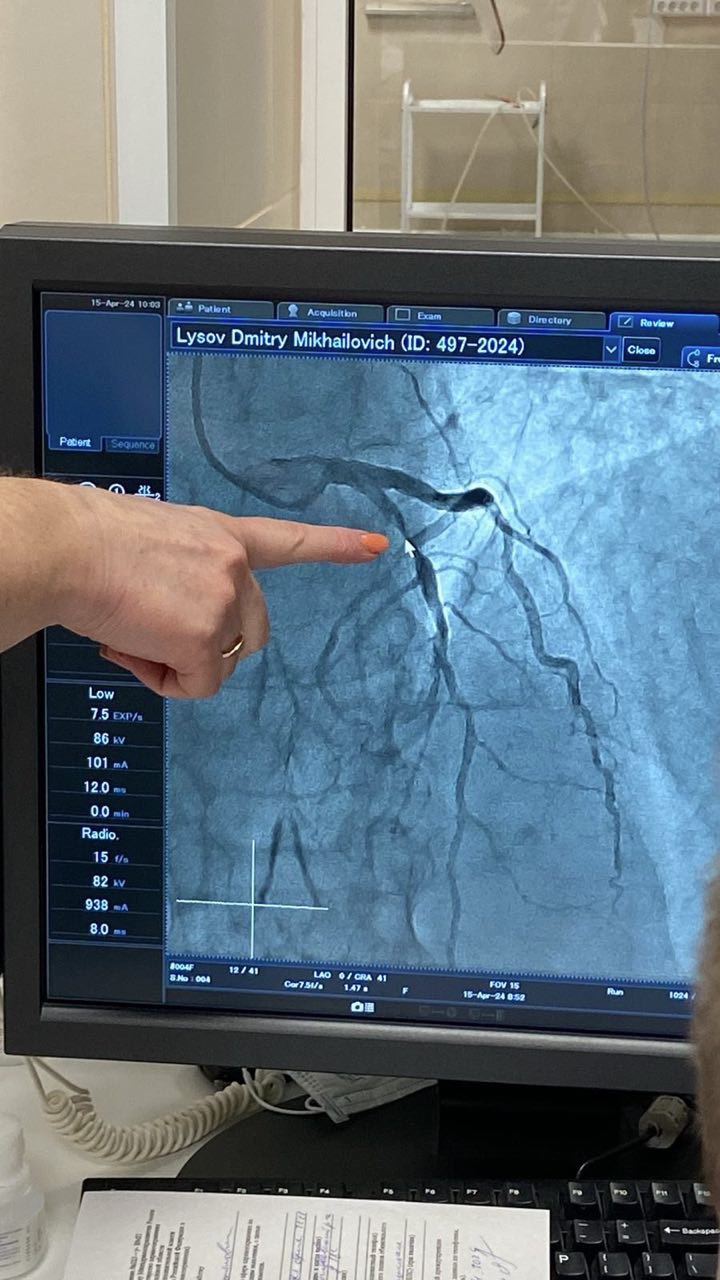

Так, прошла встреча студентов с наставником из Центральной городской больницы Арзамаса. Сначала для них состоялась экскурсия по больнице: палатам, процедурным, реанимационным отделениям. Затем студенты ознакомились с работой аппарата для проведения коронографии, искусственной почки и аппаратов МРТ и КТ. В заключение встречи в патологоанатомическом отделении студенты наблюдали за вскрытием тел умерших и проведением гистологического исследования препаратов.